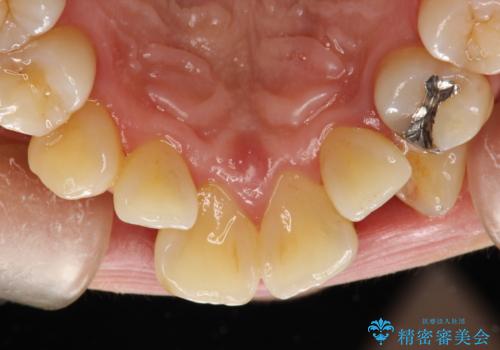

プラーク(細菌の塊)や歯石がたまると歯の表面はザラつきいてきます。そのザラつきは歯周病や虫歯菌の棲家となります。そのまま放置すると、歯肉が腫れてきたり、歯肉から出血したり、口臭が強くでたりします。とくに歯肉の境目は、歯磨きで汚れを除去することが難しく、プラーク(細菌の塊)や歯石が溜まりやすい場所です。

歯並が、がたついている場合はなおさら汚れが溜まりやすいです。矯正治療前や矯正中、定期的にPMTCをすることで、矯正治療中の歯肉トラブルを防ぐことにつながります。

- これから矯正治療を始めるため、今の状態でも歯をきれいにしておきたいとのことでした。PMTC60分コースを行いました。